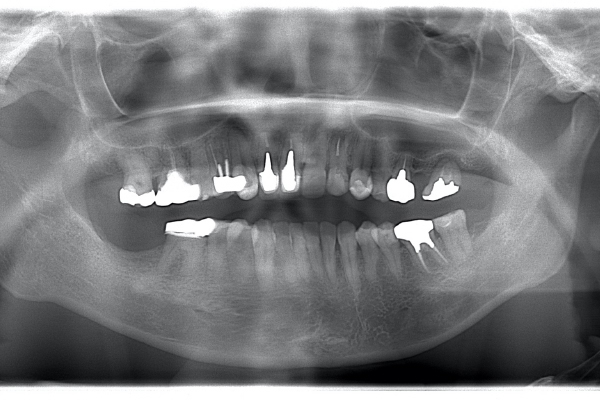

左上2は広範囲にわたってCRが充填されているのがわかります。またその周囲に透過像があり、カリエスになっていることもわかります。

| 治療前 | 治療後 |

|---|---|

![]() |

| 根の中の薬が十分に充填されておらず、根の先が周りと比べて黒くなっており、炎症があると判断できます。 | 根の中にしっかりとお薬を緊密に充填しましたが、まだ根の先に黒くなっている部分があります。 |